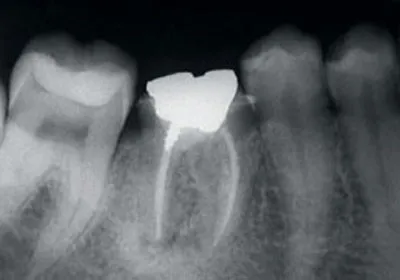

1-1a Preoperative periapical radiograph of a mandibular molar requiring endodontic retreatment prior to placement of a new crown.

1-1b Periapical radiograph taken 9 years postoperatively. Good preparation and irrigation of the canal in conjunction with a good coronal seal ensures the longevity of the treatment.